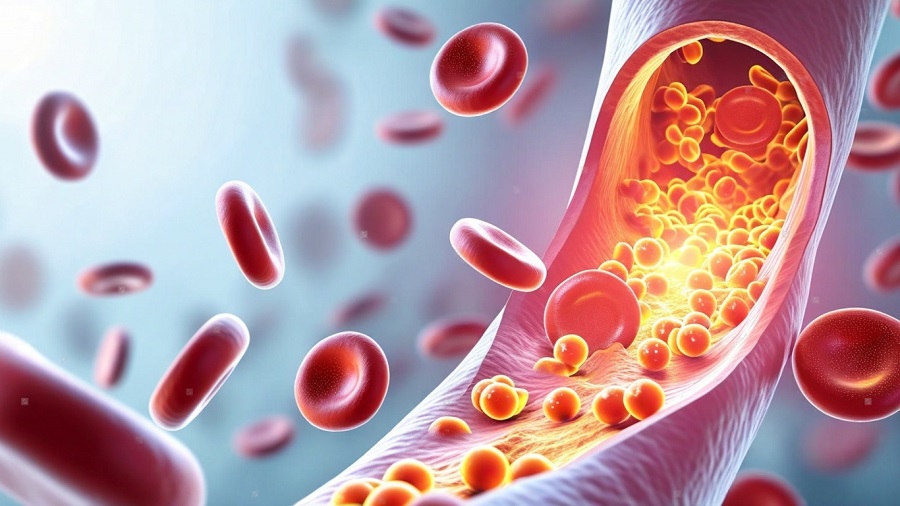

Железо входит в состав гемоглобина — белка, отвечающего за транспорт кислорода к органам и тканям. Кроме того, оно участвует в синтезе миоглобина, ферментов дыхательной цепи и множества биохимических реакций. Недостаток железа приводит к снижению работоспособности, ухудшению когнитивных функций, ослаблению иммунитета и замедлению восстановления тканей.

Подтверждённая железодефицитная анемия сопровождается снижением гемоглобина и эритроцитов, что приводит к выраженной гипоксии тканей. В этом случае клинические проявления становятся более заметными и требуют обязательной медикаментозной коррекции.